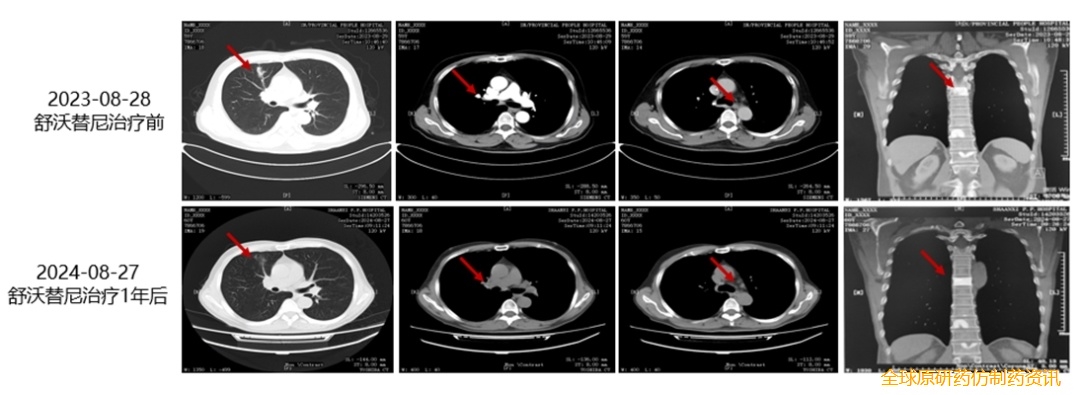

舒沃替尼治疗史:

• 2023年8月28日,予以“舒沃替尼“单药(300mg QD)靶向治疗。2024年8月复查CT示病灶较前有缩小,未见明显异常(图2)。治疗期间仅发生轻度甲沟炎,经对症处理后好转,整体安全性良好。截至发稿日,患者仍在接受舒沃替尼单药治疗,PFS已超过13个月,持续治疗时间近15个月。

图2. 患者接受舒沃替尼治疗前后影像学变化